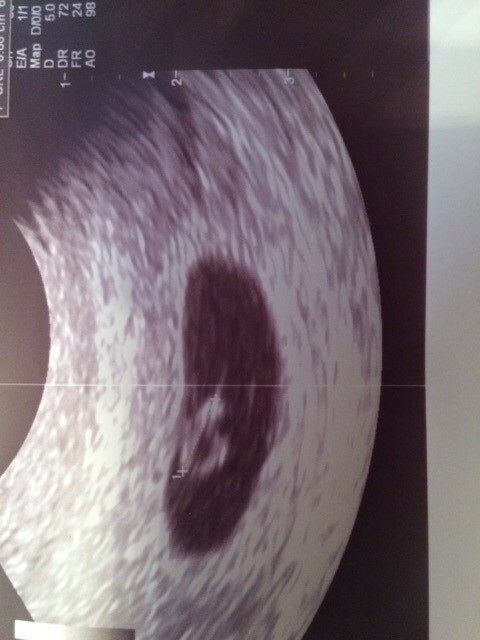

Pięknie [emoji175] rośnijcie zdrowo ! dobranoc [emoji182]Moja pamiatka z dzisiejszej wizyty.. Serduszko puka.. Wszystko jest ok. Oficjalnie jestem czerwcowka![]()